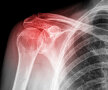

Foto 1/5